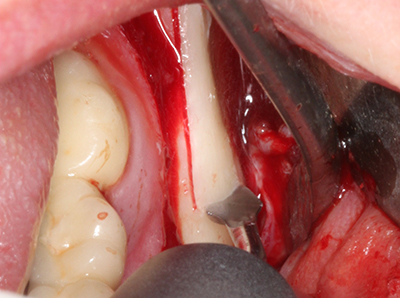

En la extracción de bloques óseos la piezocirugía también presenta ventajas adicionales: Además de la alta precisión en la osteotomía que ya se ha descrito antes, se ha comprobado que el uso de los delgados insertos de sierra resulta especialmente cuidadosas con el hueso. Frente a esto, sobre todo cuando se usan las fresas de Lindemann, cabe esperar pérdidas en la extracción significativamente más altas debido al mayor grosor de la parte frontal del cabezal (Lakshmiganthan, Gokulanathan et al. 2012). La separación basal que se necesita en particular en los injertos de bloque extraídos de forma retromolar se ve facilitada mediante sierras perpendiculares especialmente previstas a tal fin, lo que permite considerar que la cirugía piezoeléctrica es un procedimiento preciso y seguro para la obtención de bloques de hueso en el área retromolar (Happe 2007) (fig. 1-12).